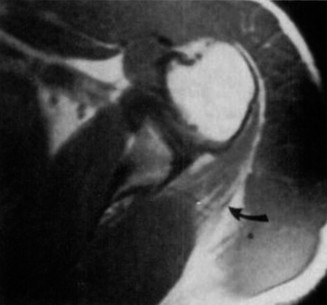

CT arthrograms of the patient’s left shoulder are shown in Figure 2–56. CRP is <3, ESR 45. The patient continues to have pain, so you decide to perform arthroscopic biopsy to obtain tissue cultures. Frozen sections show <5 PMNs per hpf, and Gram stains are all negative.

Figure 2–56

The correct answer is (B). Figure shows contrast under the glenoid component. Given the patient’s normal inflammatory markers and frozen sections combined with continued pain and loosening on CT, infection with P. acnes(an organism that is very difficult to isolate) should be investigated by holding any cultures for at least 2 weeks to see if it will eventually grow. Chocolate agar (Choice C) is mainly used for growing species such as H. influenzae and Neisseria meningitidis not P. acnes. A is incorrect since the patient’s cell count and frozen sections are clearly abnormal, therefore referral to pain clinic would not be appropriate. However, Choice D would be too aggressive an approach given that no organisms have been isolated, frozen sections show <5 PMNs per hpf, and the patient has relatively normal inflammatory markers.